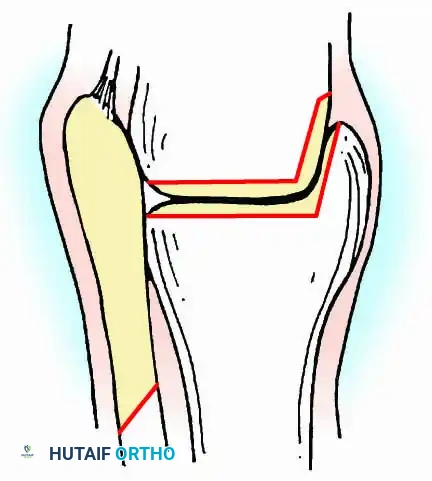

- Contour Preservation (Fishscaling): The remaining articular cartilage is meticulously denuded using curettes, and the subchondral bone is "fishscaled" or aggressively petalled with a sharp osteotome. This preserves the native ball-and-socket contour of the ankle, maximizing inherent bony stability and minimizing limb shortening.

- Planar Resection (Parallel Cuts): Two parallel cuts are made—one through the distal tibial plafond and one through the talar dome—using an oscillating saw. This technique resects a minimal amount of bone but creates perfectly flat, highly vascular cancellous surfaces that allow for excellent apposition and easy posterior translation of the talus. Extramedullary alignment guides (often repurposed from total knee arthroplasty systems) can be utilized to ensure precise, parallel resections.

* Translation: Slight posterior displacement of the talus relative to the tibia. This decreases the anterior lever arm of the foot, reducing the bending moment at the fusion site and facilitating an easier rollover during gait.